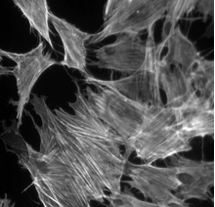

1、細(xì)胞生物學(xué):用于觀察細(xì)胞結(jié)構(gòu)、動態(tài)和相互作用。

03場景圖/實拍效果圖